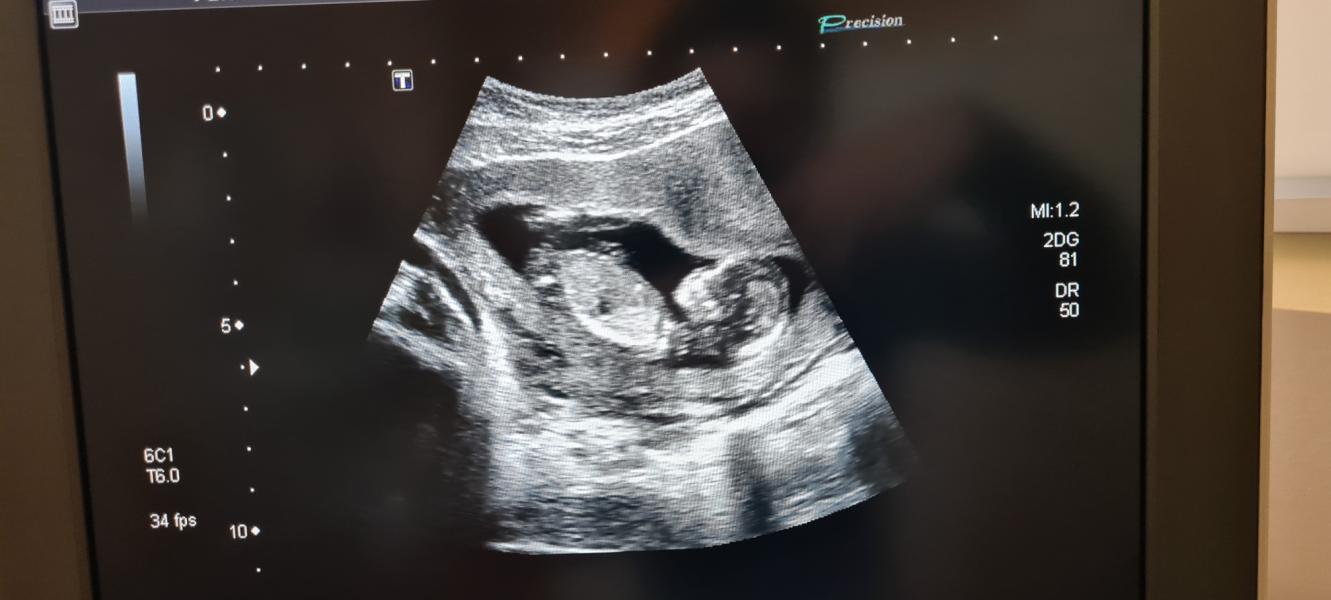

Спасибо)в перинатвльном у Кривоносовой делала,я там на учёте в жк стою)предполржили мальчика,но пока не точно )) главное не волнуйтесь, все хорошо будет 💖

Пол малыша удалось рассмотреть?